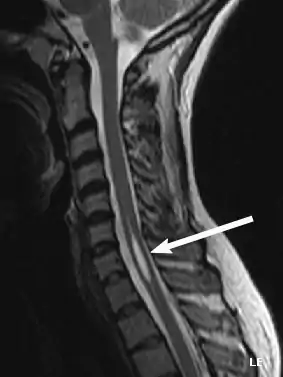

Diagnosis

Physicians now use magnetic resonance imaging (MRI) to diagnose syringomyelia. The MRI radiographer takes images of body anatomy, such as the brain and spinal cord, in vivid detail. This test will show the syrinx in the spine or any other conditions, such as the presence of a tumor. MRI is safe, painless, and informative and has greatly improved the diagnosis of syringomyelia.[19]

The physician may order additional tests to help confirm the diagnosis. One of these is called electromyography (EMG), which show possible lower motor neuron damage.[20] Note this test isn't used diagnostically for injuries to the spine but to nerves and muscles.This would be part of a patients rehab routine. In addition, computed axial tomography (CT) scans of a patient's head may reveal the presence of tumors and other abnormalities such as hydrocephalus.[21]

Like MRI and CT scans, another test, called a myelogram, uses radiographs and requires a contrast medium to be injected into the subarachnoid space. Since the introduction of MRI, this test is rarely necessary to diagnose syringomyelia.[22]

The possible causes are trauma, tumors, and congenital defects. It is most usually observed in the part of the spinal cord corresponding to the neck area. Symptoms are due to spinal cord damage and include pain, decreased sensation of touch, weakness, and loss of muscle tissue. The diagnosis is confirmed with a spinal CT, myelogram or MRI of the spinal cord. The cavity may be reduced by surgical decompression.[23]